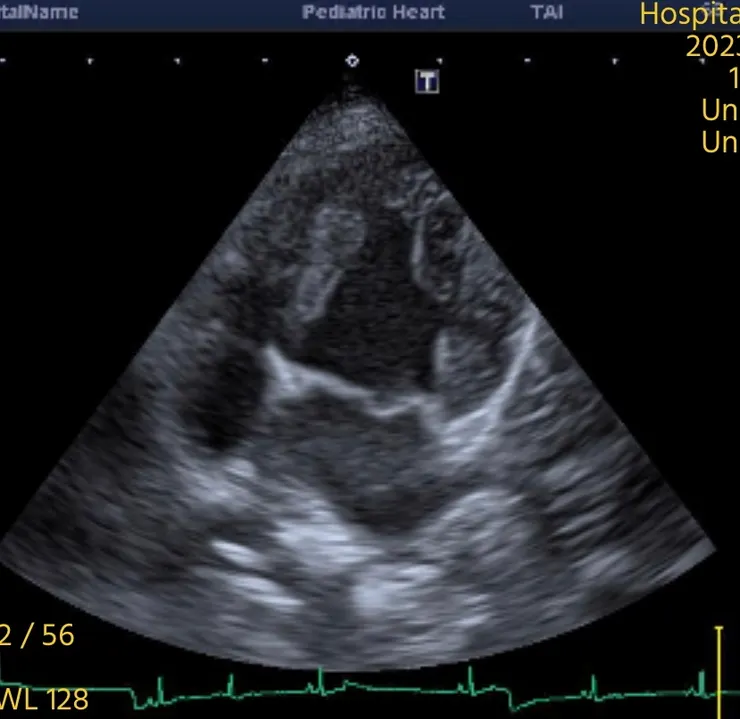

➡️心臟超音波可以幫助我們看到左心房的擴張或是腱所斷裂瓣膜退化等, 詳細一點的話也可以評估左心房的壓力用來輔助我們判斷心因性肺水腫的可能性, 但心臟超音波無法看到肺臟狀況。所以最終還是會需要用xray 去看肺部的狀況, 證實有肺積水。

心臟超音波 二尖瓣退化

心臟超音波二尖瓣繞流